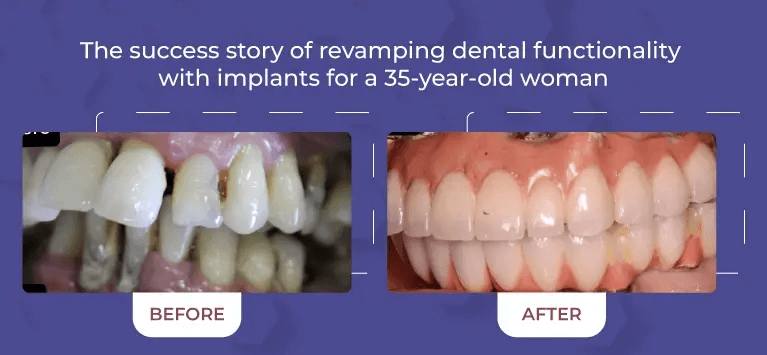

Comprehensive Services

From routine cleanings and preventive care to advanced cosmetic and restorative dentistry, we offer a full range of dental services to keep your smile healthy and vibrant.